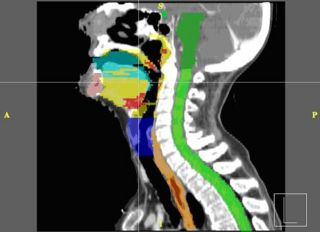

Interactive Segmentation

Modern radiotherapy requires manual contouring of both target structures and healthy normal tissues, to ensure adequate coverage with minimal radiation side effects. The goal of this project is to evaluate if 3d-slicer is capable of providing a comfortable user interface needed for physicians and physicists to perform manual contouring.